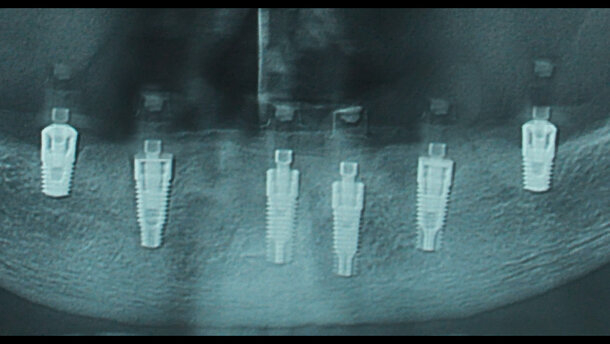

Si presenta presso il nostro studio la paziente A.B., 54 anni, non fumatrice e in buona salute generale, poiché desidera riabilitare l’arcata inferiore richiedendo una protesi fissa. Dall’esame clinico e radiografico (Fig. 1) si evidenziano elementi dentali residui nel settore anteriore con grave compromissione endo-parodontale e una notevole atrofia ossea nei settori posteriori. L’altezza ossea verticale disponibile per l’inserimento implantare in sede 36 è di 7 mm, e in sede 46 è di 6,5 mm. Vengono proposte alla paziente procedure di ricostruzione ossea preimplantare, che vengono rifiutate; pertanto, si presenta una proposta di riabilitazione implantoprotesica con l’utilizzo di impianti di lunghezza standard nel settore anteriore e di lunghezza 6,5 mm nei settori diatorici.